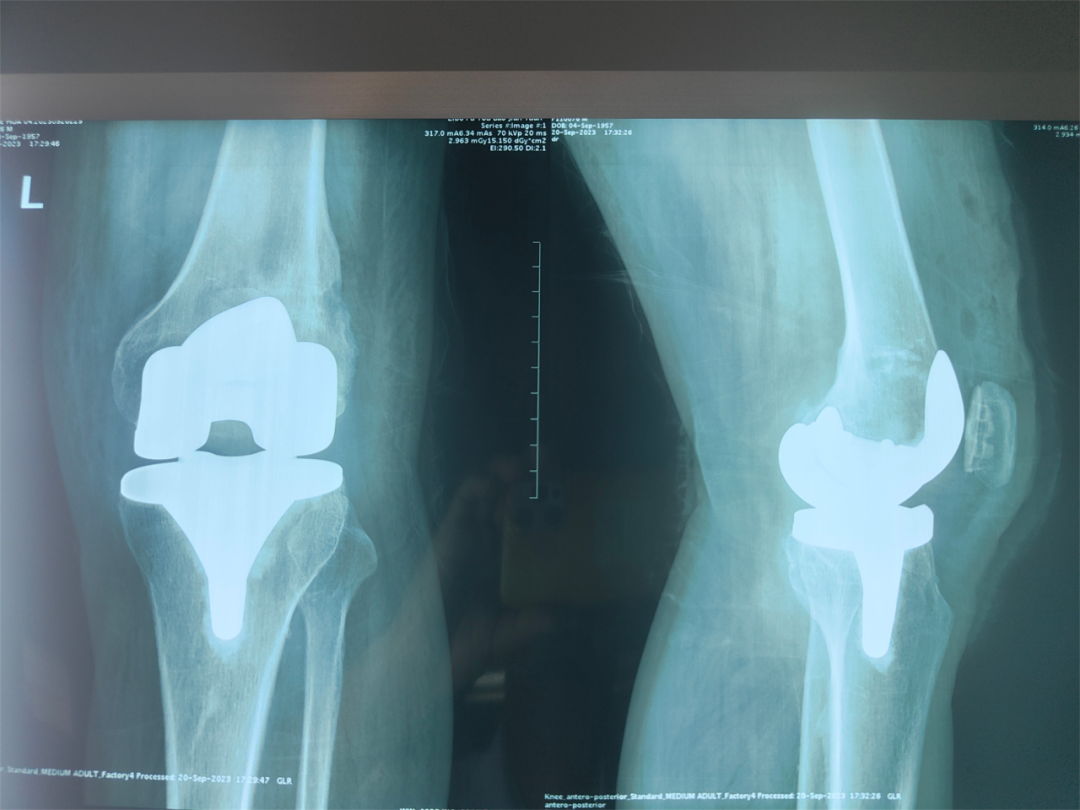

来院后,李光胜组织骨外科团队与北京美德瑞骨科中心、康复医学科共同讨论认为,病人现有膝外翻、膝关节有既往手术粘连挛缩,属于难度较大的膝关节置换手术;内固定螺钉固定已经13年,单独取出创伤、难度也较大,可以一次住院、手术在关节置换、截骨的同时进行内固定取出手术。患者及家属慎重考虑后,决定住院治疗。入院后,综合诊断为“左侧膝关节病、半月板损伤、关节游离体、外翻畸形,高血压病,2型糖尿病”。仔细认真的术前准备后,在心血管内科、神经内科、呼吸内科等多学科会诊保驾护航下,骨外科团队、美德瑞骨科中心团队通力合作,如期进行了手术。术中发现,13年后的螺钉跟预期的一样,被骨痂包埋的严严实实,取出困难,膝关节内有多个大小不一的游离体,膝关节面磨损严重,最终,凭借高水平的技术,顺利完成股骨内固定螺钉取出、孔道植骨、左膝关节游离体摘除+膝关节置换手术。